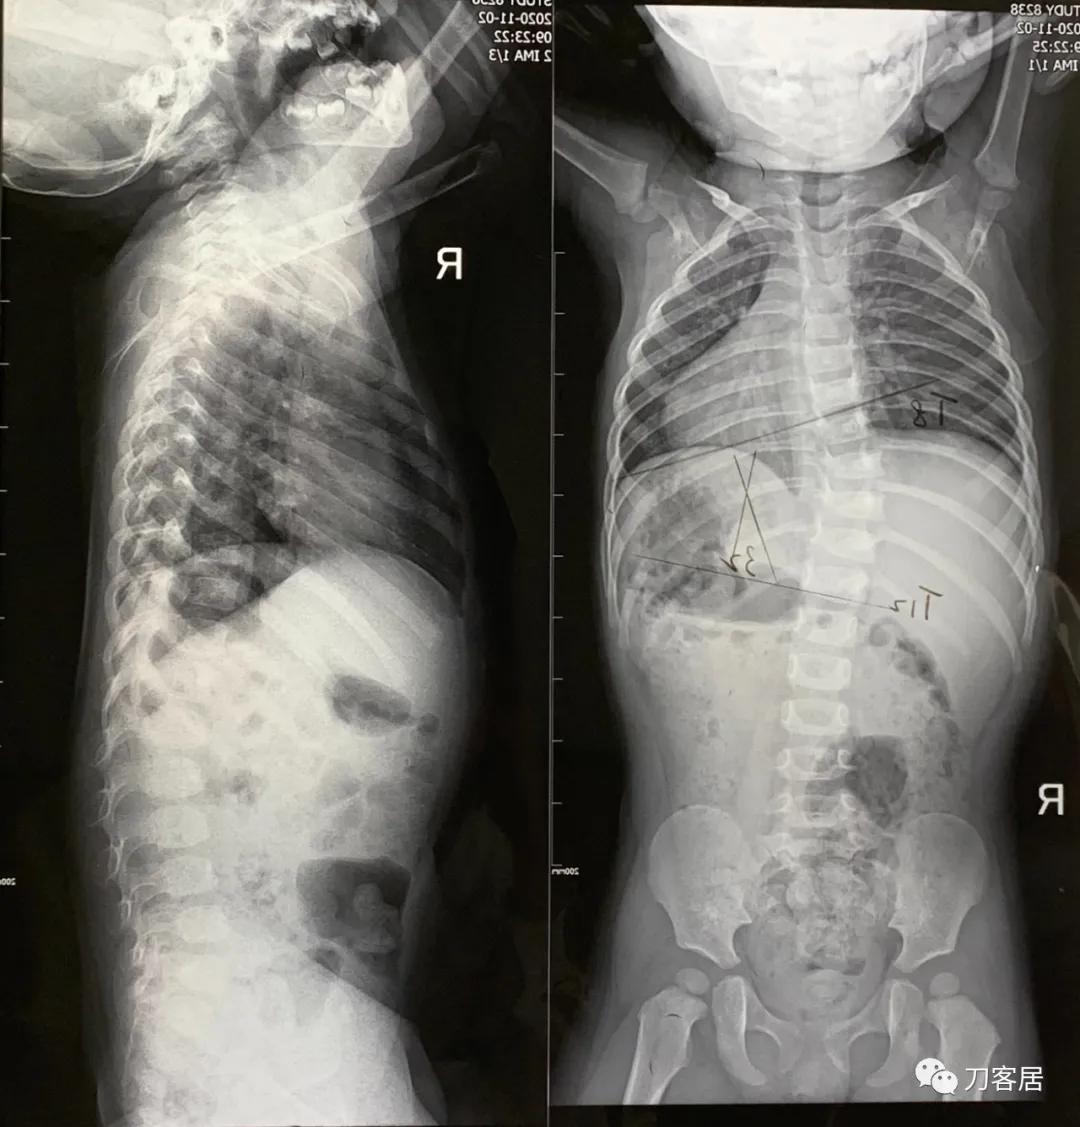

图7. 2020年9月4日脊柱全长X线正位片显示T7-L1胸腰段脊柱侧凸,凸向右侧, Cobb角35度。

图8. 2020年9月4日脊柱全长X线侧位片。

图9. 2020年11月2日脊柱全长正侧位X线片,显示T8-12向右侧侧凸,Cobb角32度。